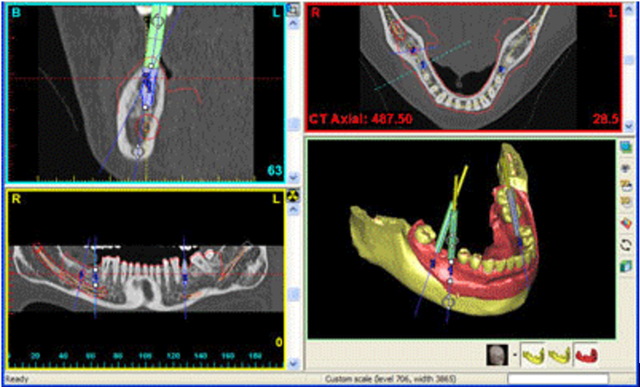

*Manejo de la imagen bidimensional –el radiológico–, o tridimensional –los demás–.

*Interfase de uso de los cuerpos tridimensionales bidimensional, en base a gráficos que representaban los cortes del objeto.

El comienzo de las aplicaciones como la cirugía e implantología guiadas y asistidas por ordenador, introducidas a raíz de los trabajos elaborados en el Proyecto Phidias.